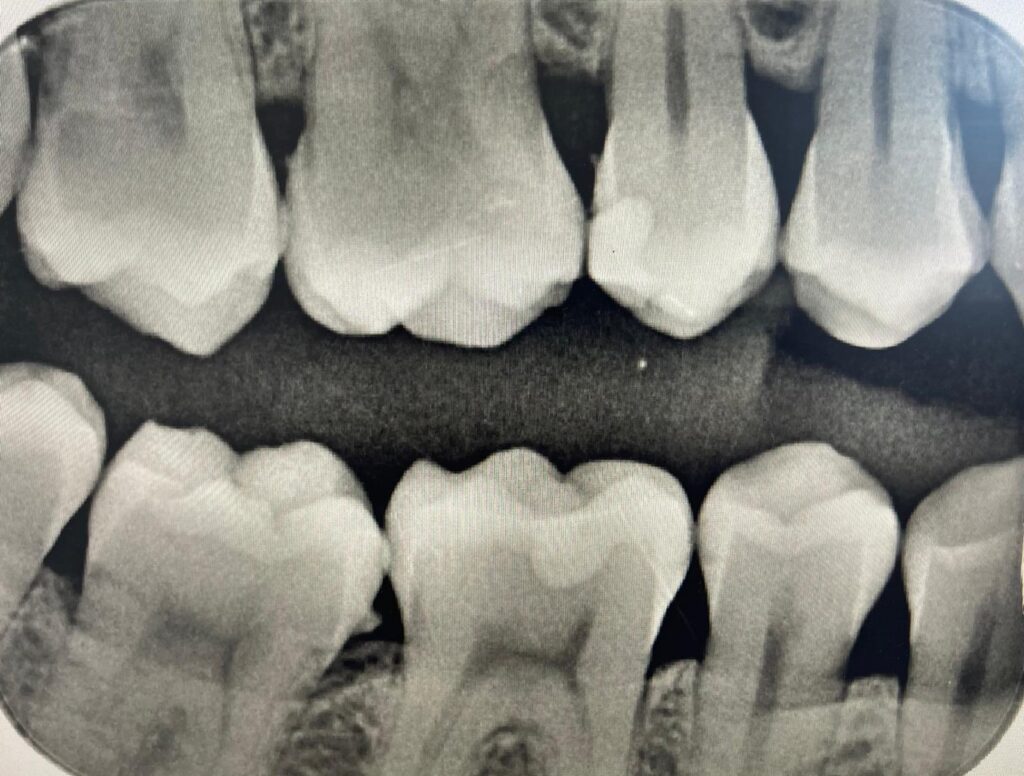

RTG punktowe

RTG punktowe to podstawowe narzędzie diagnostyczne stosowane we współczesnej stomatologii. Pozwala na szybkie i precyzyjne uwidocznienie pojedynczych zębów oraz okolic przyległych struktur kostnych. Dzięki RTG punktowemu lekarz może ocenić obecność ubytków próchnicowych, stan wypełnień, kondycję korzeni oraz wykryć początki stanów zapalnych. To badanie jest niezwykle ważne w planowaniu leczenia endodontycznego czy protetycznego, ponieważ dostarcza szczegółowych informacji niezbędnych do skutecznej terapii. W naszym gabinecie stosujemy najnowocześniejsze urządzenia cyfrowe, które gwarantują wysoką jakość obrazu przy minimalnej ekspozycji na promieniowanie, co czyni badanie nie tylko dokładnym, ale i bezpiecznym dla pacjenta. RTG punktowe w Poddent to szybka diagnostyka, komfort oraz pełna precyzja w planowaniu leczenia.